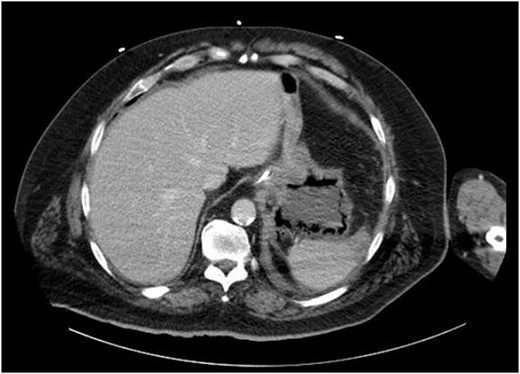

On evaluation, the patient was afebrile, tachycardic to 107 bpm, with BP 112/63 and RR 21. On exam, he appeared diaphoretic and had left upper quadrant tenderness without rebound or guarding. He was otherwise alert and oriented. His white blood cell count was 22.5 with 13.1 bands, and lactate of 6.2, which improved with IV fluid resuscitation. Computed tomography (CT) abdomen and pelvis demonstrated pneumatosis of the proximal gastric wall (Fig. 1), and mild portal venous gas. He was started on antibiotics and antifungals; a nasogastric tube was placed for decompression, and he was started on parenteral nutrition; however, he failed to improve clinically, with continued abdominal pain and tenderness, and persistent tachycardia. A repeat CT after 5 days of treatment redemonstrated gastric wall pneumatosis (Fig. 2), though with resolution of the portal venous gas.

Repeat CT of the abdomen and pelvis: decompression of the stomach with persistent gastric pneumatosis.